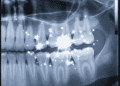

Leia MaisDetailsA radiografia é um dos pilares fundamentais da prática odontológica moderna, desempenhando um papel crucial na identificação de condições que...

Leia MaisDetailsA radiologia dentro da odontologia deixou de ser apenas um recurso complementar e passou a ocupar um papel central no...